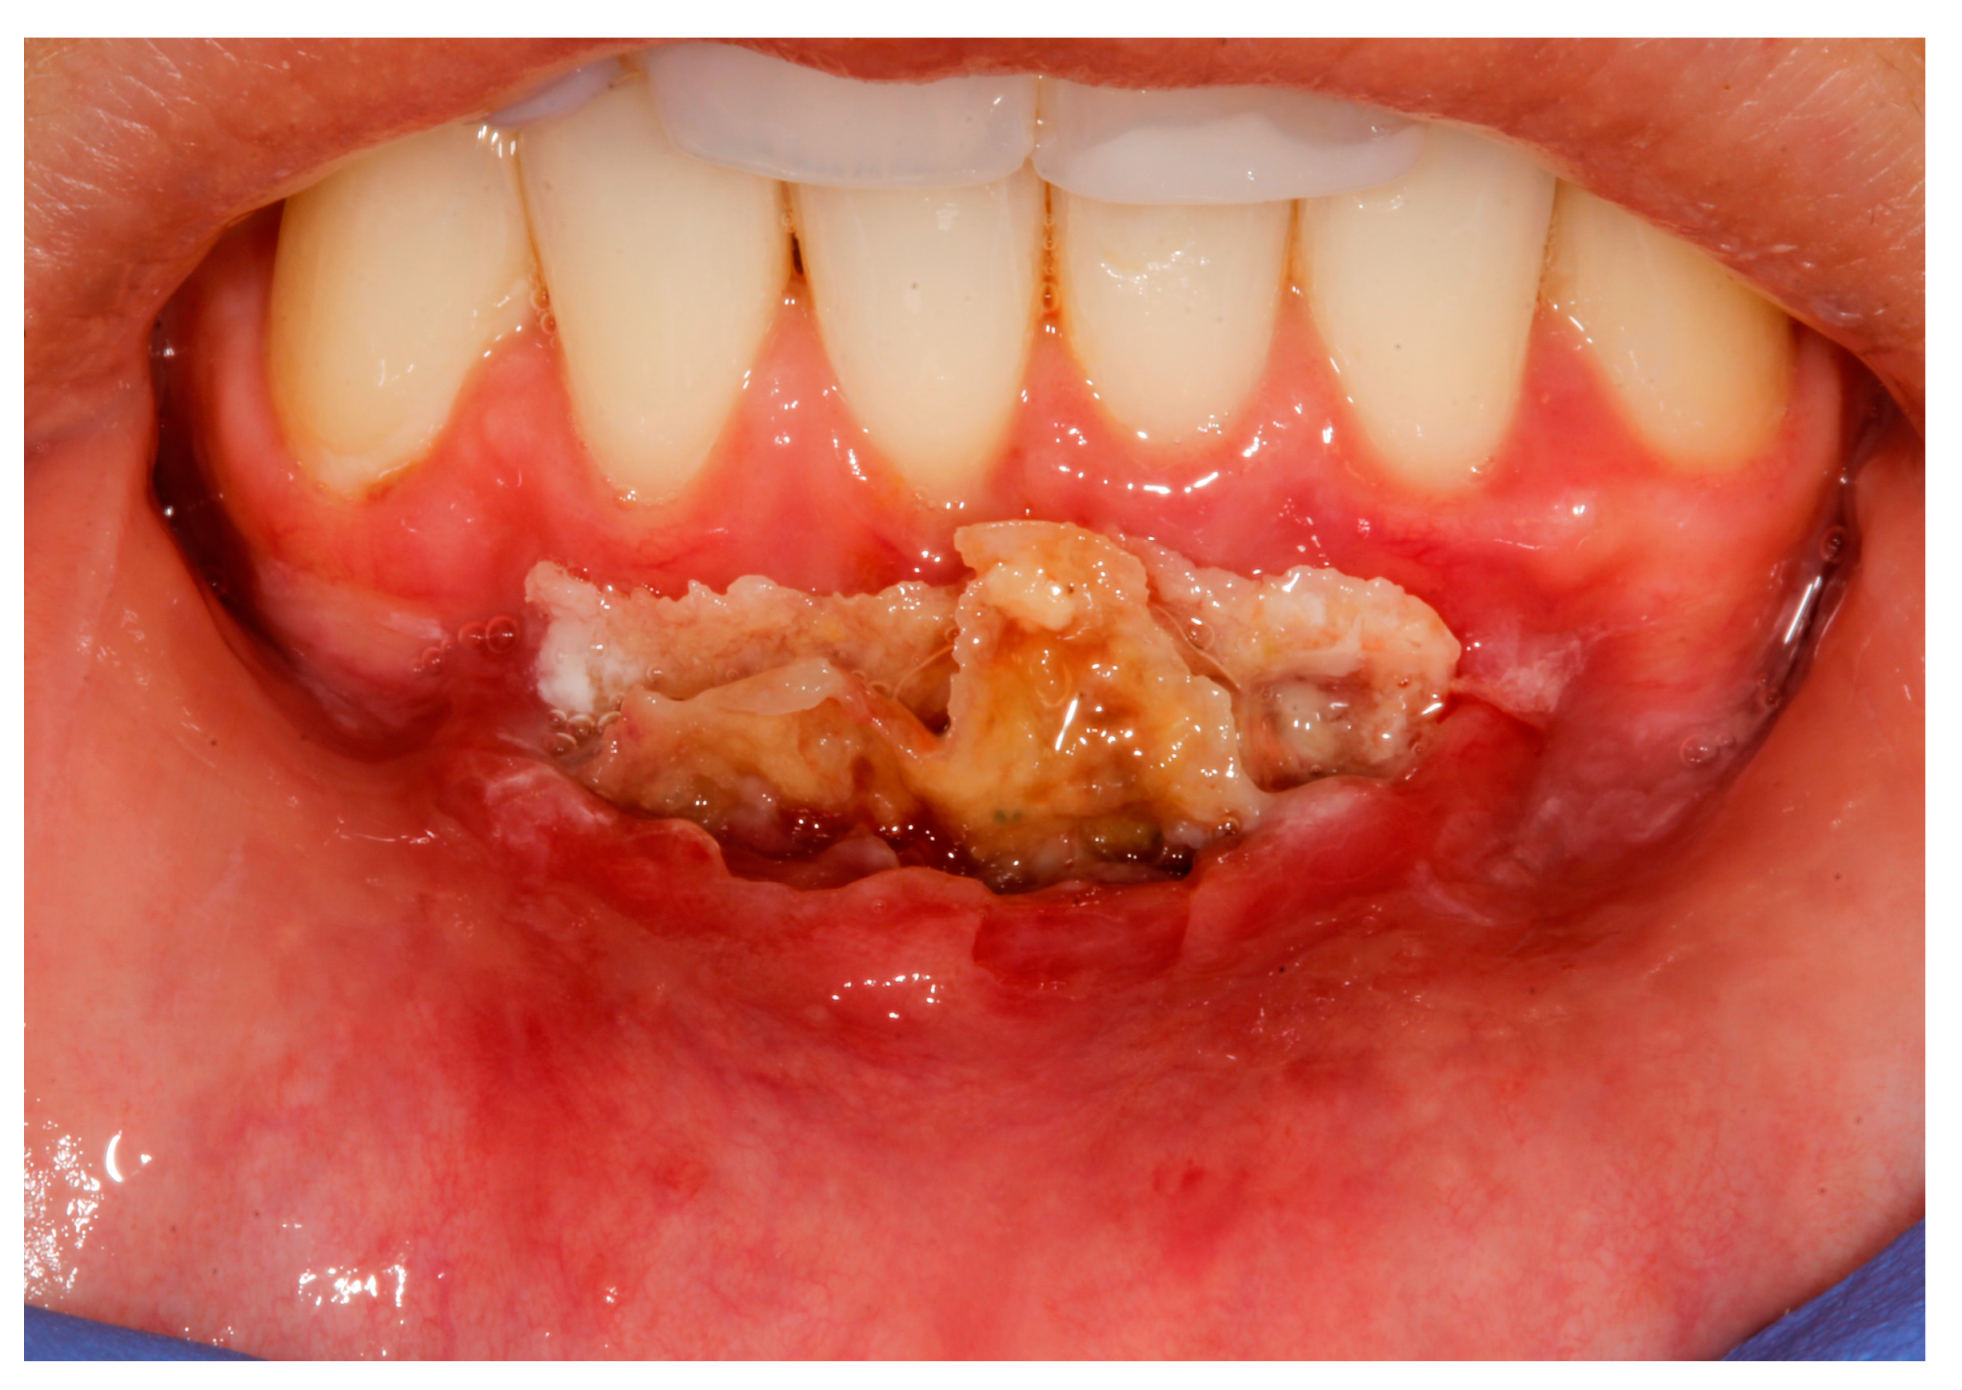

- (a)

- deep partial thickness incision (blade parallel to the periosteum) made at the level of the external insertion of the frenulum;

- (b)

- elimination of superficial mucous tissue and muscle of the frenulum;

- (c)

- a series of detached points with periosteal anchorage for the apical positioning of the lining mucosa of the lip and the second intention healing of the exposed periosteum.